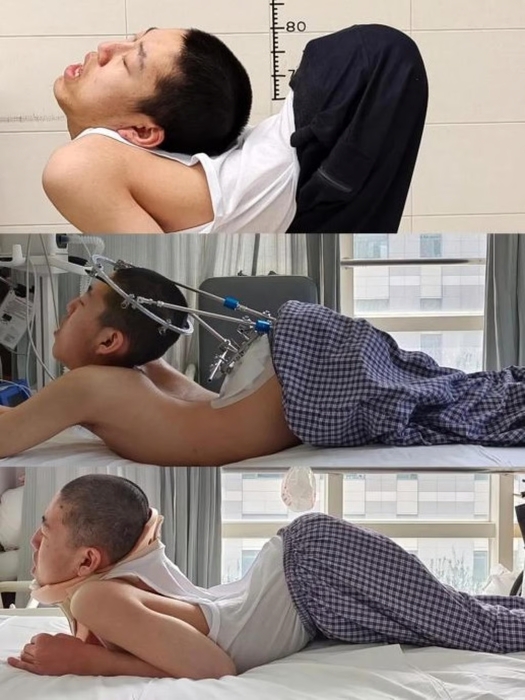

2004年、中国山東省(さんとうしょう)の小さな村で生まれたチャン・イェンチェン氏は、先天性の筋疾患により小学生の頃から首が徐々に後方へ反り、上半身がアルファベットの「Z」の形に折れ曲がっていった。脊椎が著しく後方に曲がったことで胸部と腹腔が極端に狭まり、内臓も圧迫されて健康状態は悪化し始めた。

2024年、脊椎奇形治療の権威、リャン・イージェン教授のもとで治療が始まり、チャン・イェンチェン氏の回復への道が開かれた。梁教授は腰椎、頚椎、股関節、胸部の骨を切除して再配置するという4回に及ぶ超難度の手術を今年6月までに実施。約180度に曲がっていた脊椎はついに真っ直ぐになり、チャン氏は毎日6時間のリハビリを続けた結果、歩行できるまでに回復した。

手術によって心臓と肺の機能も正常に戻った。リャン教授は「一般の人をはるかに上回る忍耐を示した」と称賛し、リハビリに耐え抜いたチャン氏に拍手を送った。

チャン氏は「生まれ変わったような気分だ」と喜び、「普通の人間になれたことで、これまでの苦痛がすべて価値あるものに感じられる」と語った。さらに来月には大学に復帰し、大学院への進学も目指す意向を示した。